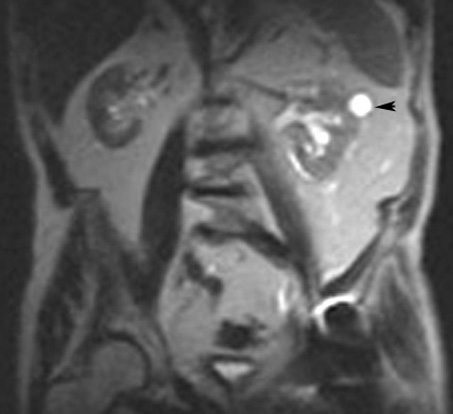

MRI: is useful when US is equivocal and contrast CT could not be done because of renal failure.